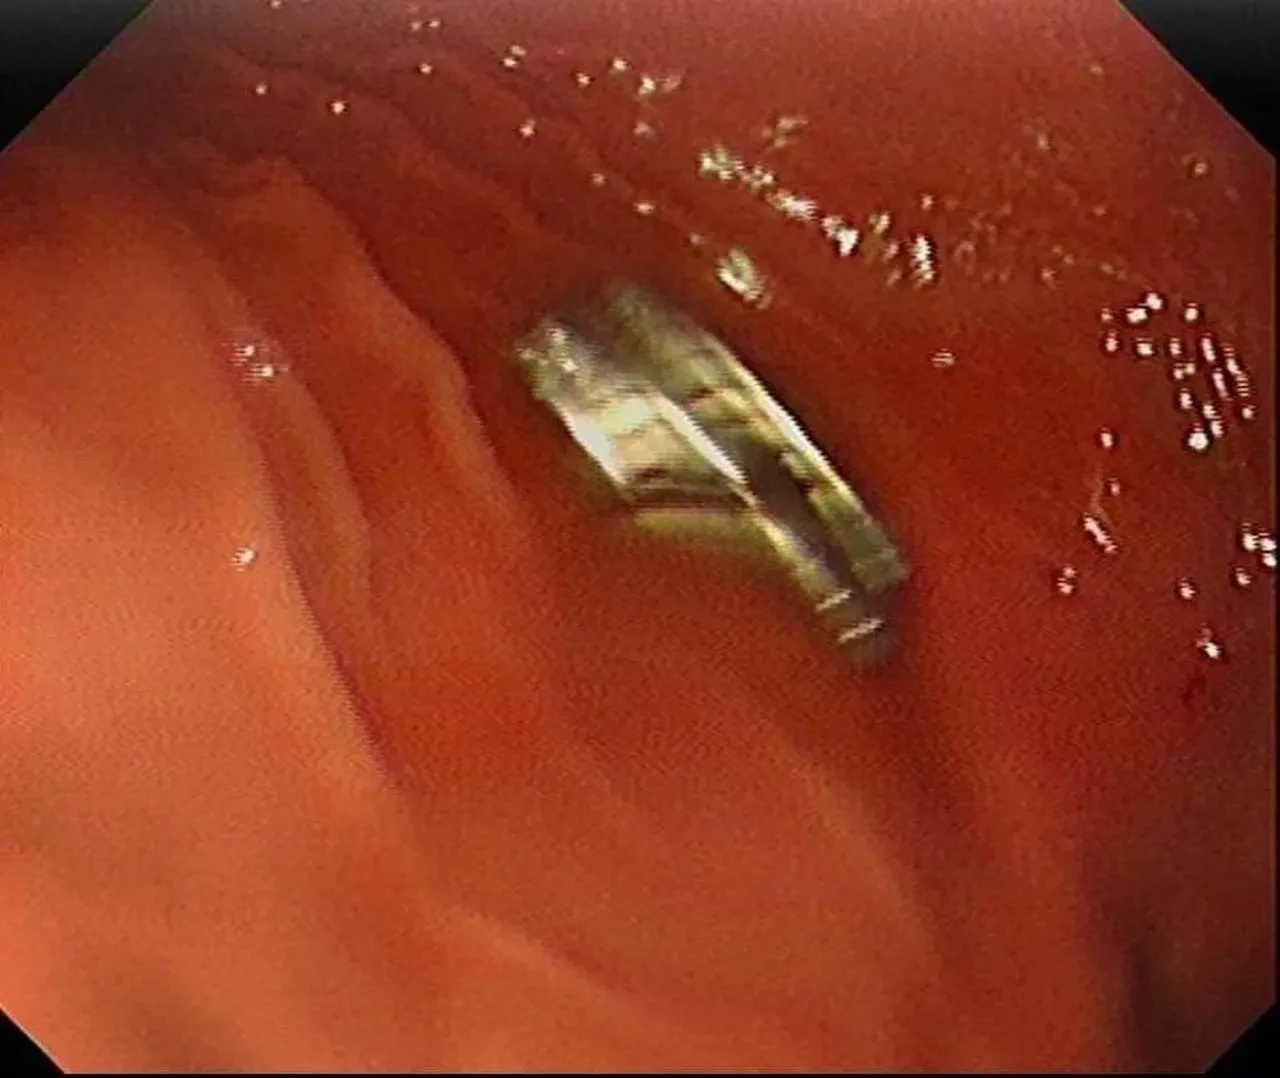

Erzurum’da 3 yaşındaki çocuğun rahatsızlanması sonrası aile hemen hastaneye başvurdu. Erzurum'dan Erzincan'a sevk edilen çocuğun boğazında yabancı cisimler tespit edildi.

Fırat Üniversitesi Çocuk Gastroenteroloji Hepatoloji ve Beslenme Bilim Dalı Başkanı Prof. Dr. Yaşar Doğan, çocuk hastanın yemek borusuna yapışmış 19 mıknatısı endoskopik yöntemle çıkardı. Mıknatıslar uzun süre yemek borusunda takılı kaldığı için yemek borusu ve mide girişinde zedelenmeler olurken, çocuğun sağlık durumunun iyi olduğu ve taburcu edildiği öğrenildi.